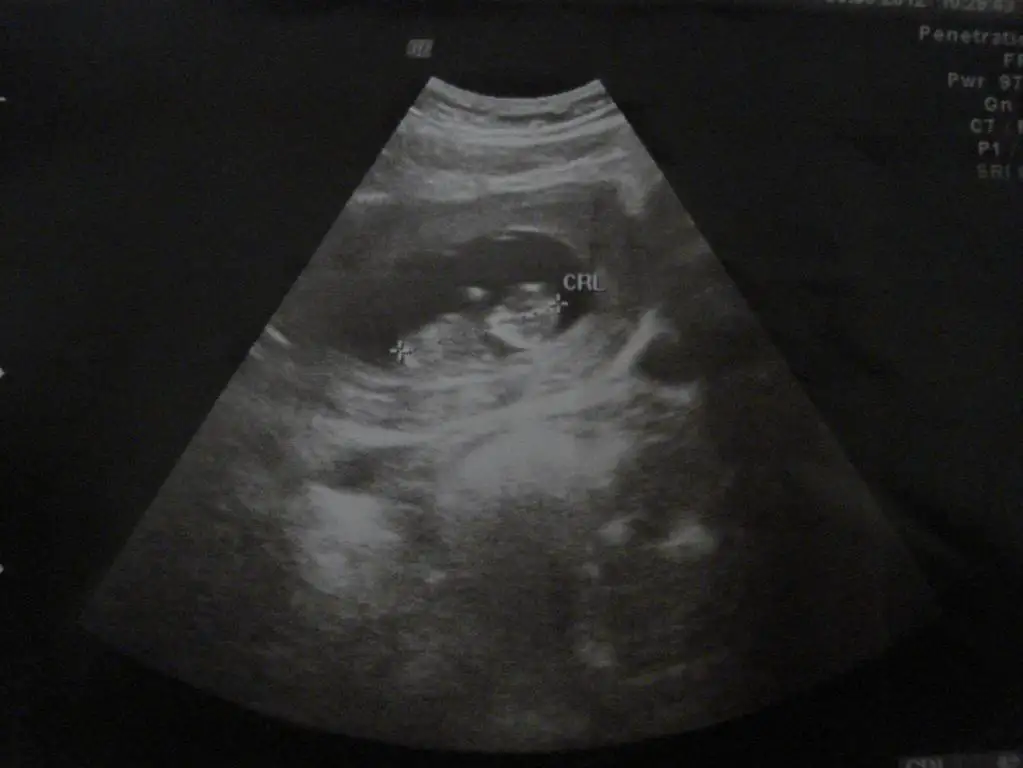

resmlerde nub cıkıntısı gozukmuyo sadece bebegin tam goruntusu olanda bi çıkıntı var gibi ama cok uzak nette degil ama bana kız gibi geldi tabi bu işin tecrubelisi orkdm

evet orada tam 12 haftalık :) ben anlayamadım 3 tane çıkıntı görüyorum orda :) inş dediğin gibi olur. evet bide poz vermiş valla :)

Evet canım çıkıntılardan biri bacak,diğer ikisinde ben de tereddüt ettim ama benim gördüğüm kordon değilse erkek gibi=)